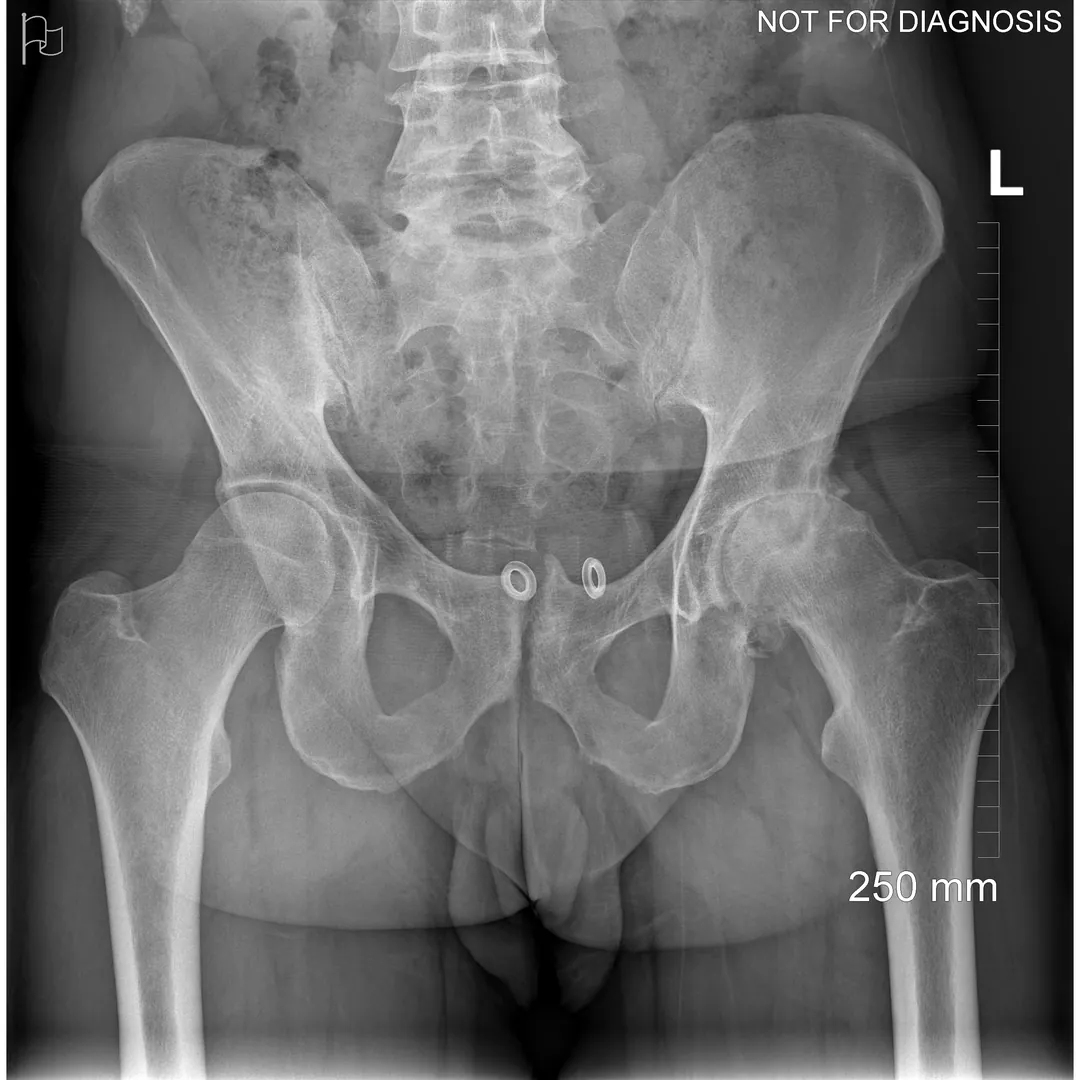

Dr Grammatopoulos will review your X-rays and other imaging carefully to determine whether hip resurfacing is an appropriate option for you.

- Am I a candidate for hip resurfacing based on my X-rays and bone quality?